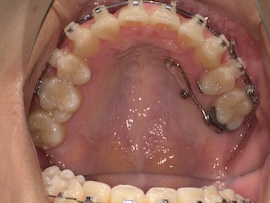

左上の7番目を抜歯してから約9ヶ月が経過しましたが、代わりに活かしていきたい親知らずが出てこないのでついに牽引(歯茎を切って引っ張り出す)をすることになりました。

内側の装置が新しくなるので今回は型取りをして準備を進めていきます。

右上の6番目にバンド(金属の輪っか)を装着するためブラケットは一時的に外しています。

左上の奥に打っていた矯正用アンカースクリューですが、今回も安定せず揺れてきてしまったので抜くことになりました。

ある程度噛み合わせは良くなってきたのであとはゴムかけだけでも問題ないとのことです。